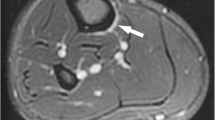

Eighty-six tibias showed abnormalities on MRI indicating a stress injury. The MRI abnormalities in all 86 tibias corresponded to the location of the patients’ clinical symptoms. None of the 86 tibias showed decreased cortical density, endosteal thickening, or a cortical fracture line on radiographs. Thirty-three of the 86 tibias showed periosteal reaction on radiographs. Thirteen of these 33 tibias showed concordant periosteal reaction that corresponded to the location of the patient’s clinical symptoms and MRI abnormalities (Fig. 1). Twenty of these 33 tibias showed a discordant periosteal reaction that did not correspond to the location of the patient’s clinical symptoms and MRI abnormalities (Fig. 2). The radiographic appearance of the concordant and discordant periosteal reaction is summarized in Table 3.

Thirty-two-year-old male marathon runner with pain and focal tenderness in the proximal tibial diaphysis. a Lateral radiograph of the tibia shows periosteal reaction (arrow) at the proximal tibial diaphysis. Corresponding b sagittal and c coronal fat-suppressed T2-weighted fast spin-echo MR images of the tibia show bone marrow edema (large arrows) and periosteal edema (small arrows) in the proximal tibial diaphysis. Note that the location of the patient’s MRI abnormalities corresponds to the location of the periosteal reaction. d Corresponding axial fat-suppressed T2-weighted fast spin-echo MR image of the tibia shows bone marrow edema (large arrow) and periosteal edema (small arrows) in the tibial diaphysis. Also note the signal abnormality (arrowhead) within the posterior tibial cortex

In the 13 tibias with concordant periosteal reaction, the periosteal reaction was located in the proximal diaphysis in 5 tibias, the mid diaphysis in 7 tibias, and the distal diaphysis in 1 tibia. The periosteal reaction was located on the anterior cortex in 1 tibia, the posterior cortex in 7 tibias, and the medial cortex in 5 tibias. The periosteal reaction was best seen on the lateral view in 9 tibias, the anteroposterior view in 2 tibias, and the oblique view in 2 tibias. Two of the 13 tibias with concordant periosteal reaction showed Fredericson grade 3 stress injuries on MRI, while the remaining 11 tibias showed Fredericson grade 4 stress injuries.

There was a strong association between the presence of concordant periosteal reaction on radiographs and the presence of various MRI findings indicative of a severe tibial stress injury. The presence of intracortical signal abnormality, which corresponds to a Fredericson grade 4 stress injury, was the MRI finding most strongly associated with the presence of concordant periosteal reaction. Patients with concordant periosteal reaction on radiographs were 26 times more likely to have signal abnormality within the tibial cortex on MRI than patients without concordant periosteal reaction.